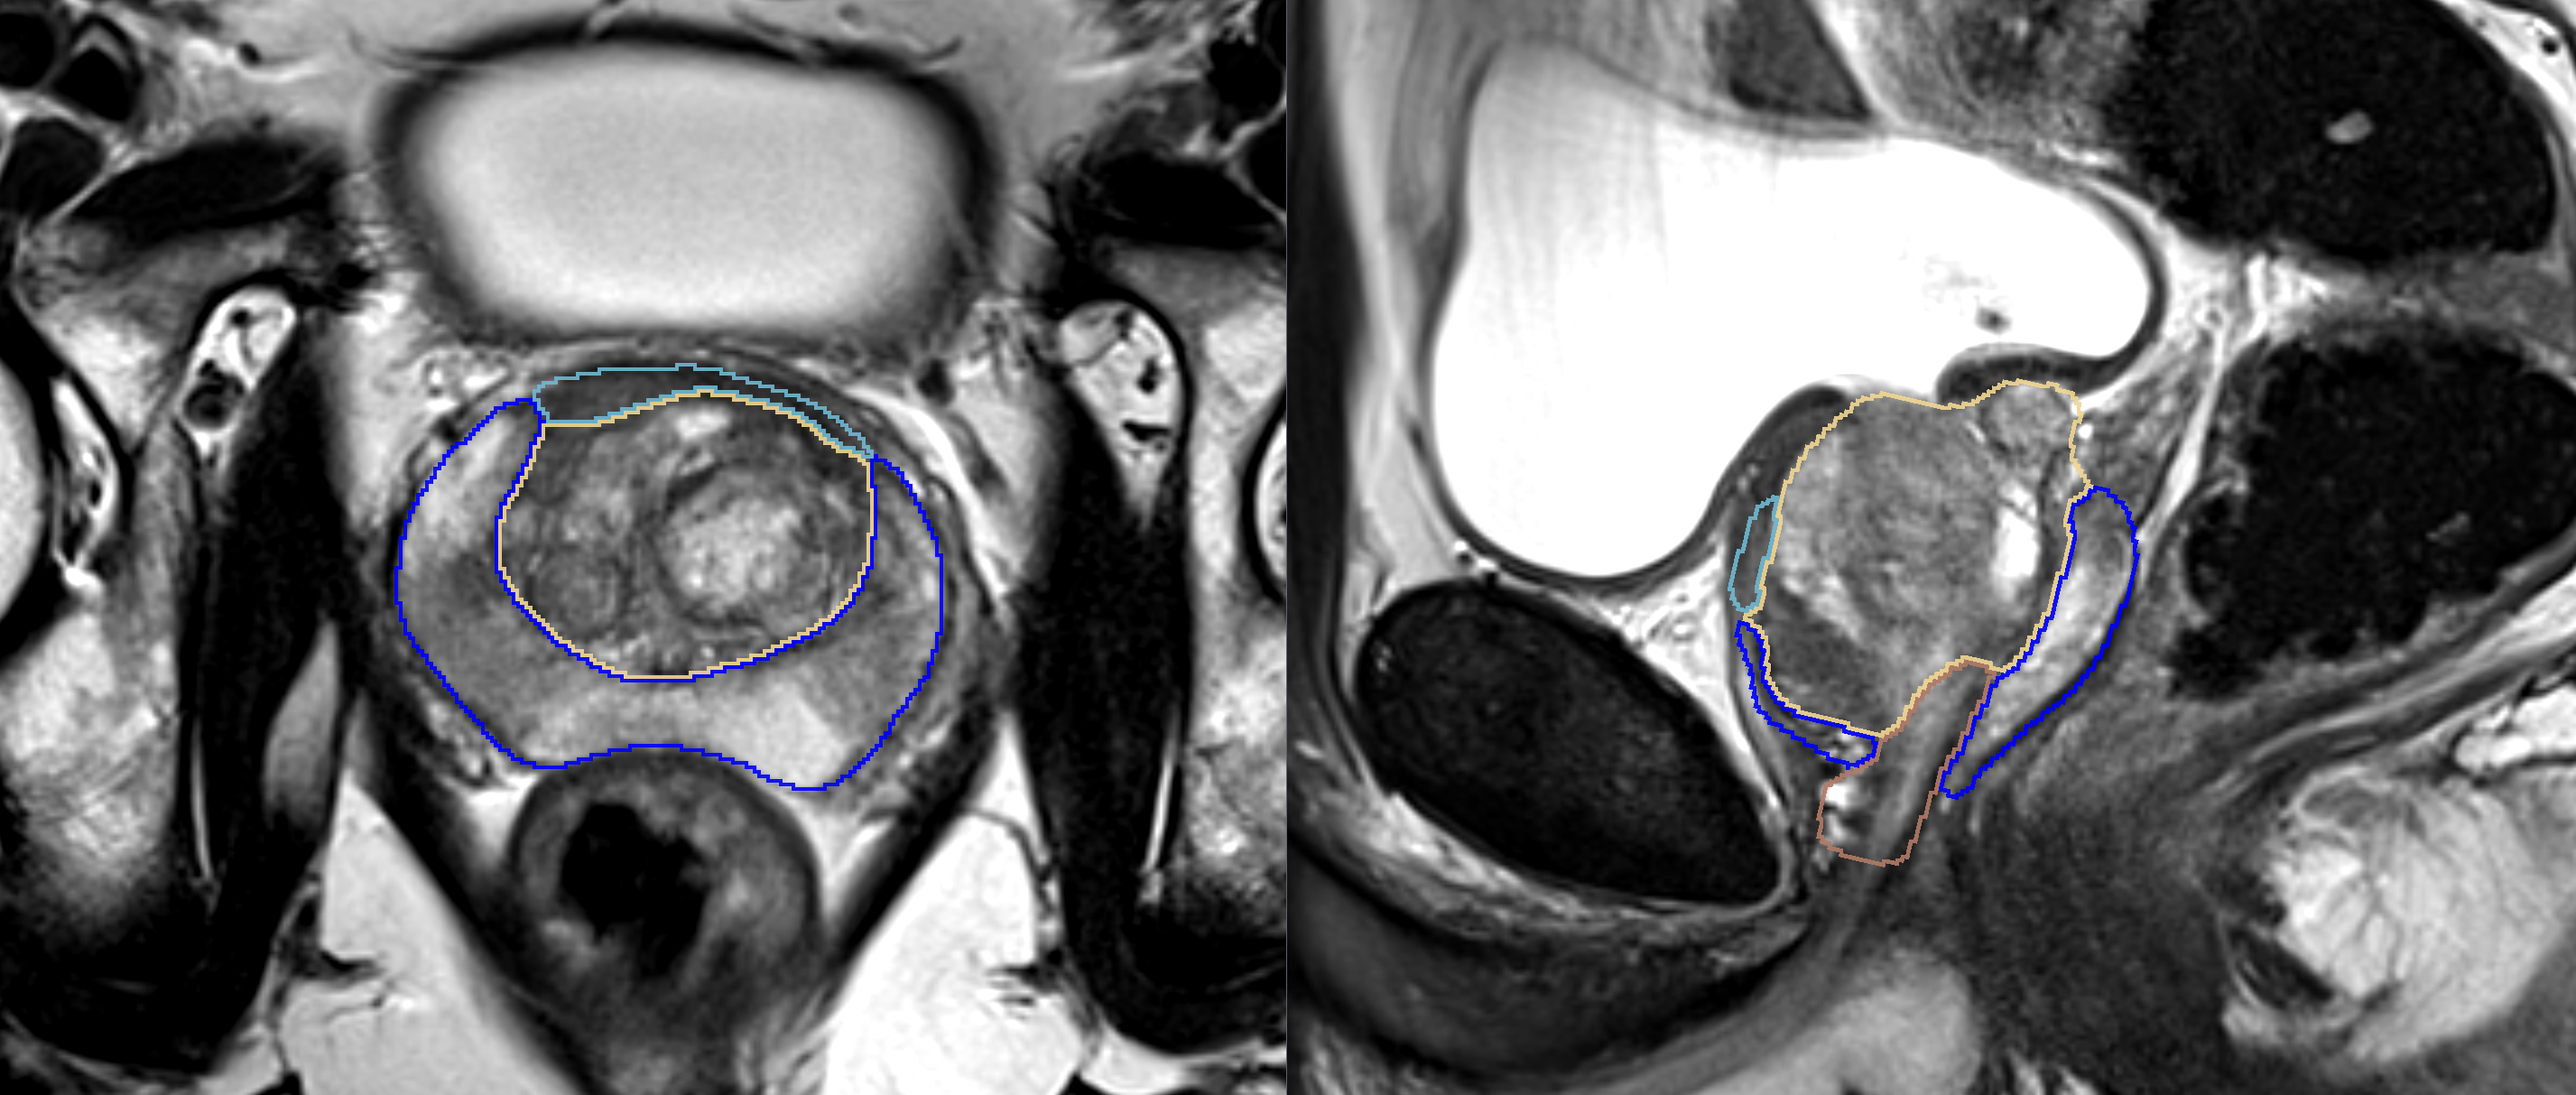

The goal of this project is to create and evaluate variants of a CNN for multi-label segmentation of prostate zones in MR images. The prostate zones are essential for lesion classification and therapy planning.

After successful segmentation, a sector map could be extracted that is used for PI-RADS reporting. This has the potential to automate and better standardize prostate lesion location reporting.

- Improvement of current segmentation result, especially for the anterior fibromuscular stroma (AFS)

- first results on more training data and with different models look promising

- Obtained meaningful results for the AFS .